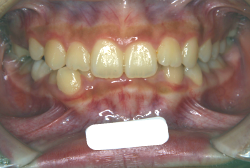

「歯並びの凸凹を直したい」という主訴で来院したケースです。診断の結果、たしかに「叢生」という隙間が足りないと言うことが原因の凸凹症例でした。

しかし、それ以上に問題なのは「前歯の噛み合い方が深すぎる」という症状で、初診の歯の正面写真を見ると下の前歯が全く見えません。こういう症状を矯正学では「過蓋咬合(かがいこうごう)」と言います。過蓋咬合を放置すると、将来的に顎関節に悪影響を与えるとされており、顎関節症の原因因子の一つです。また下の前歯の先端が、上の前歯の裏側の歯茎と強く接触するため、歯周病の原因にもなります。

検査の結果、凸凹が軽症なため非抜歯で矯正すること可能と判断、マルチブラケット装置にて治療しました。治療後は歯並びが綺麗になっただけでなく、噛み合わせ的にも正しい状態が確立しています。